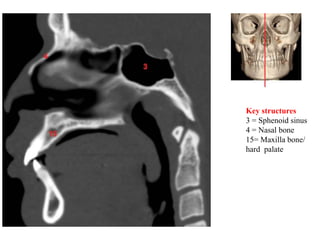

Key structures

3 = Sphenoid sinus

4 = Nasal bone

15= Maxilla bone/

hard palate